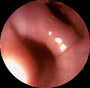

Divertículos del cuerpo esofágico Los divertículos del cuerpo esofágico se observan preferentemente en los dos tercios inferiores del esófago. Cuando se localizan en los 5 cm por encima del esfinter esofágico inferior, reciben el nombre de divertículos epifrénicos. En algunos casos estas lesiones son congénitas y representan una forma frustada de fístula esofageotraqueal. Los divertículos por tracción, poco frecuentes en los países desarrollado se deben a deformaciones o cicatrices del esófago resultantes de enfermedades inflamatorias crónicas del mediastino. Los divertículos del tercio medio del esófago suelen ser de pequeño tamaño, de forma redondeada y de cuello ancho, lo que explica que raras veces retengan alimentos. Son relativamente frecuentes. Las manifestaciones clínicas de los divertículos son muy variables y dependen fundamentalmente de su tamaño y localización. La mayoría de las veces son asintomáticos, pero del del cuerpo esofágico pueden ocasionar disfagia y a veces regurgitación, síntomas habituales del divertículo de Zenker. Los grandes divertículos del tercio medio del esófago también pueden producir disfagia y regurgitaciones El diagnóstico se establece por lo general radiológicamente. El contraste de bario permite ver con facilidad el tamaño y la situación de la bolsa diverticular. La endoscopia agrega escasa información, salvo en el caso de que se sospeche la presencia de un cáncer. Endoscópicamente, los diverticulos del tercio medio del esógafo suelen ser de pequeñas dimensiones y cuello ancho (*) Los divertículos epifrénicos suelen presentar un cuello estrecho aunque su tamaño puede alcanzar grandes proporciones (*) produciendo incluso una reducción de la luz esofágica. Como los divertículos epifrénicos son divertículos por pulsión, la pared diverticular está formada por una fina capa mucosa lo que aumenta el riesgo de perforación al practicar la endoscopia. TRATAMIENTO Los divertículos asintomáticos no requieren tratamiento. En los pacientes con disfagia o serios problemas de regurgitación está indicada la cirugía. En la mayor parte de los casos de divertículos epifrénicos, se practica una funduplicatura si la miotomía llega al esfínter esofágico inferior.